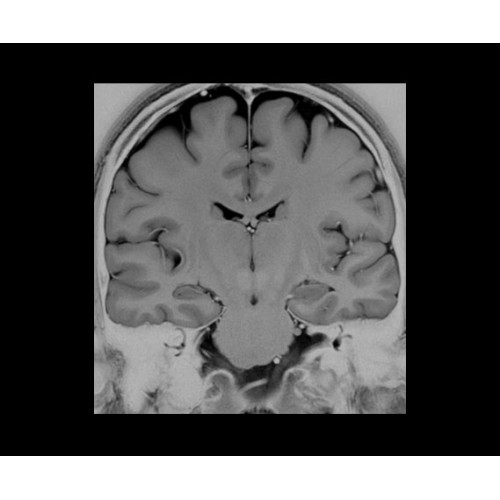

• NeuroWorks — универсальное решение для визуализации анатомии головного мозга, позвоночника, сосудов и периферических нервов с четкой дифференциацией тканей.

• HyperWorks — пакет програмных приложений, который включает технологию HyperSense для поразительной визуализации и скорости.

• ImageWorks — повысит производительность МРТ благодаря визуализации высокого качества с MAGIC, четкими результатами пост-процессинга с READYView.